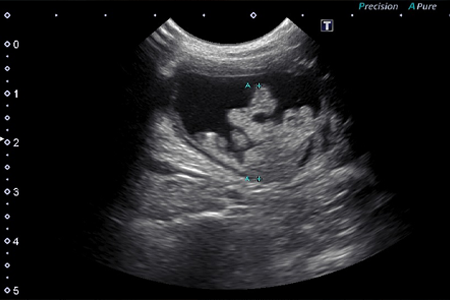

超音波検査で局所リンパ節、肝臓、脾臓などへの転移の有無を確認します。レントゲン検査にて肺転移を確認する必要があります。

CT・超音波検査・レントゲン検査では腰下リンパ節の腫大、前立腺肥大、骨格への転移(特に腰椎)の発見が可能です。

犬の場合は殆どが膀胱壁の筋層に浸潤する「表在性乳頭状腫瘍」や膀胱壁に浸潤した病変を示します。約6割弱が尿道へ拡がりを見せ、約三割弱が前立腺へ拡がりを見せます。膀胱内腫瘤では膀胱漿膜の平滑が保てているか、膀胱の漿膜面に不整が認められないかを調べます。漿膜面に不整が見られるばあいは膀胱壁の外にまで腫瘍が達している可能性があります。

膀胱三角部を含む膀胱頚部近くに腫瘍では、尿管開口部障害による水腎や水尿管が生じている場合もあるため、超音波で腎臓、尿管も合せて評価を行います。